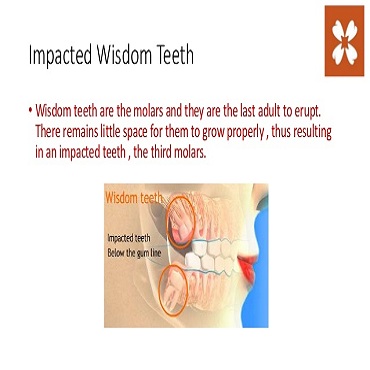

Shagun Dental Care in Lucknow offers a host of treatments and cures for a wide range of dental ailments faced by the patients. Few of the dental procedures they offer range from inducing fillings and repairs in the tooth, undertaking root canal surgeries, applying crowns (caps), bridges and implants, teeth whitening as well as extractions (surgical removal) of cavities/milky /disfigured/wisdom teeth.